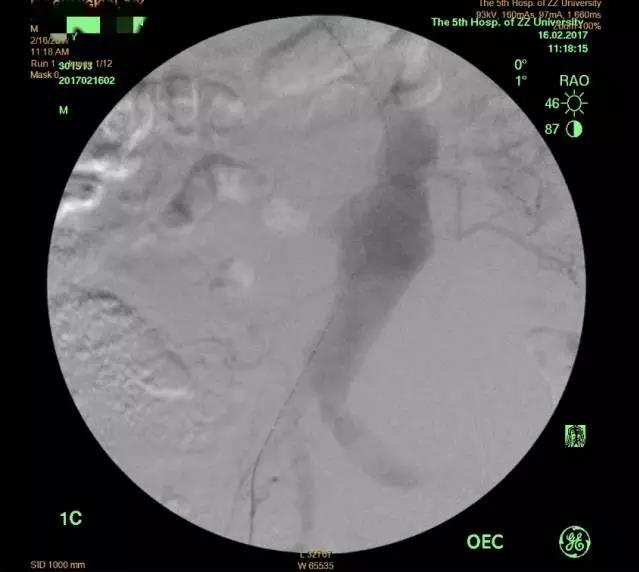

图3 术中造影:支架植入前

经过术前的精细测量和精心设计,王兵教授亲自操刀手术,整个过程异常顺利,仅耗时2小时便顺利完成手术。不仅成功隔绝瘤体及破口,还成功保留了患者双侧肾动脉及右侧髂内动脉,避免了内脏及臀部的缺血(术中造影 图3、4)。在血管外科施敏护士长带领的护理团队精心护理下,目前患者正处于康复期,腹痛消失,各项生命体征平稳。